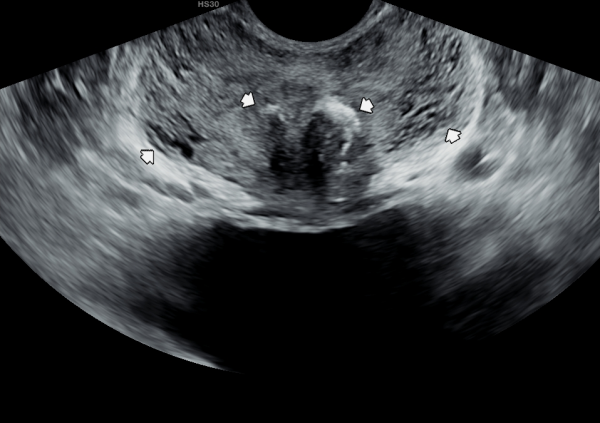

5년전 내원 당일 검사한 경직장 전립선 초음파 사진상 좌우 사정관 입구의 막혀있는 미세 결석들과 전립선관의 순환장애로 전립선의 낭종들이 관찰되는 사진입니다.

A transrectal prostate ultrasound image taken on the day of the initial visit five years ago shows microcalcifications blocking the openings of both ejaculatory ducts, as well as prostatic cysts caused by impaired circulation in the prostatic ducts.